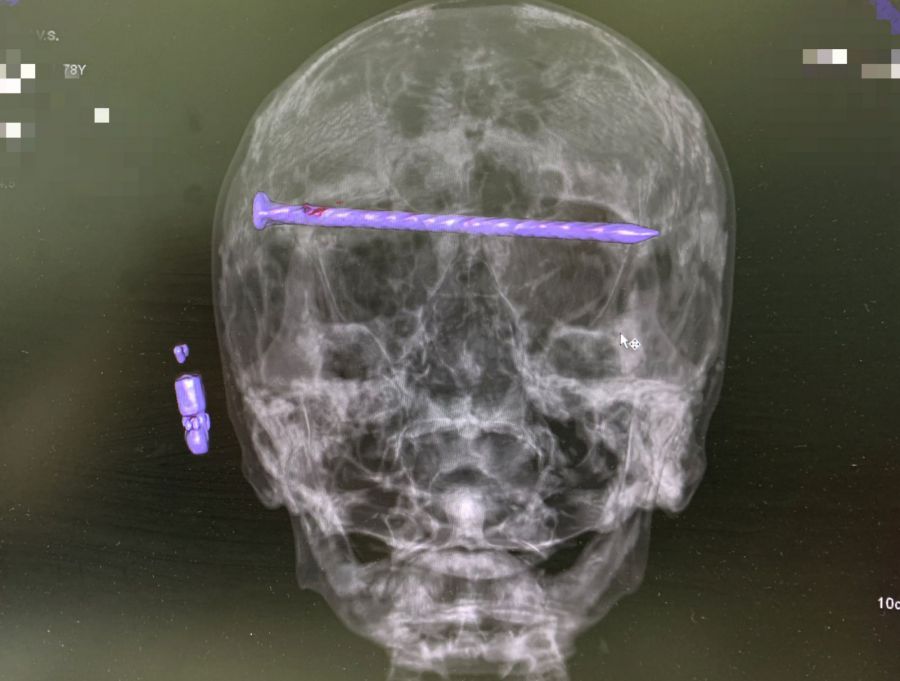

Мужчина поступил в приёмный покой Городской больницы № 1 Нижнего Тагила в тяжёлом состоянии, причиной которого была травма головы. В ходе компьютерной томографии медики увидели в костях черепа гвоздь, который прошёл через обе глазницы от правого до левого виска. Длина металлического предмета достигала 15 сантиметров. Ситуация осложнялась повреждением твёрдой оболочки мозга и сдавлением глазных яблок.

Чтобы спасти пациента, бригада специалистов во главе с заведующим нейрохирургическим отделением ГБ № 1 Нижнего Тагила Дмитрием Неволиным провела экстренную операцию. Врачам удалось извлечь гвоздь, сохранить уральцу зрение и целостность костей черепа. После вмешательства пациенту провели контрольную компьютерную томографию и перевели его в отделение.